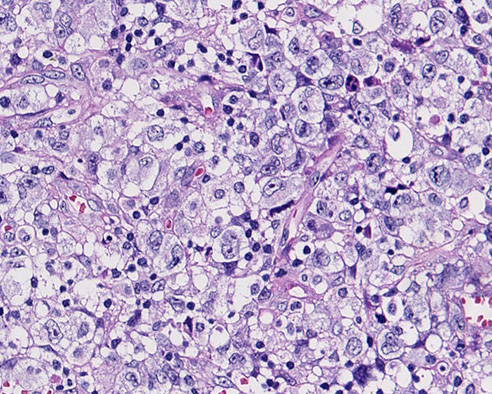

- 馬蹄形(偏心性), 腎臓様, またはドーナツ状などの核をもつ目印細胞「hallmark cells」をさがす。

- hallmark cellsは通常大型であるが、小型のものも存在する。

- しばしば核近傍に好酸性のゴルジ野が見つかる。(CD30, ALK染色などで陽性となる)

- 形態学的亜形が存在することに注意。小型腫瘍細胞からなるものから巨核あるいは花環状の多核細胞からなるものまである。

- 形態にかかわらず核クロマチンは繊細で、あまりめだたない。(明るい核が多い). 核小体は複数個で不規則。

- リンパ節内では実質内にびまん性分布をしめす。しばしば類洞浸潤が特徴的。

- 腫瘍細胞は結合性,粘着性で, organized patternをとって増殖し, 未分化癌や悪性黒色腫の転移と誤診断することがある。